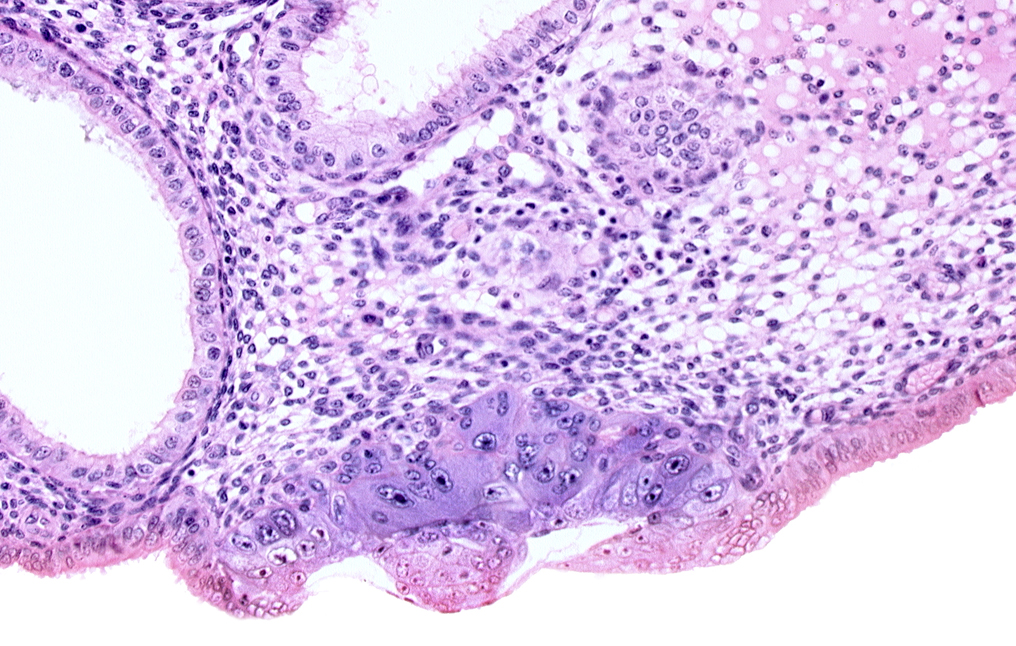

Carnegie Embryo #8020 | Location: 06-02-02

Keywords: amniotic cavity, blastocystic cavity (blastocoele), embryonic disc, endometrial epithelium, endometrial sinusoid, membranous trophoblast at abembryonic pole

Source: The Virtual Human Embryo.